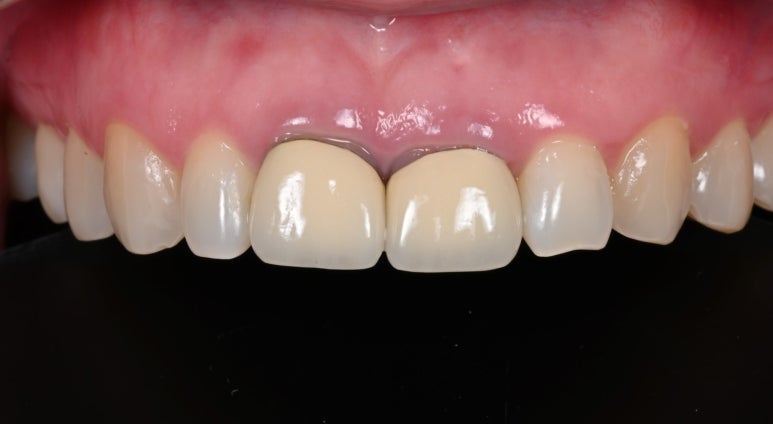

5. 최종 크라운 장착

새로 제작된 크라운을 장착합니다.

환자분께서 색상과 모양에 만족해하셔서 특별한 수정없이

치료를 마무리할 수 있었습니다.

25.09.11 치료 후